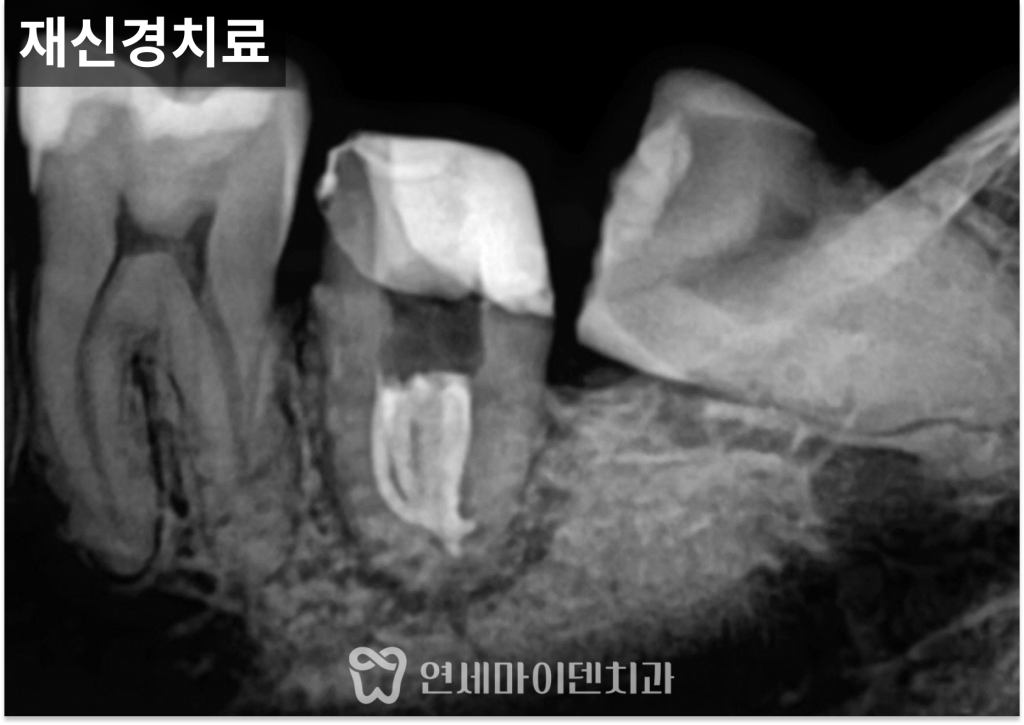

신경치료 전, 구조를 먼저 만드는 이유

손상된 치아는

외부와 내부가 그대로 연결된 상태이기 때문에

그대로 신경치료를 진행하면

세균이 계속 유입될 가능성이 있습니다.

그래서 먼저 레진을 이용해

치아 외형을 임시로 복원하는

레진 댐(dam)을 형성했습니다.

이 과정을 통해

외부 세균 유입을 차단하고,

보다 안정적인 환경에서

신경치료를 진행할 수 있습니다.

이러한 준비 과정은

신경치료의 성공률을 높이는 데

중요한 단계입니다.

포스트와 크라운으로 기능 회복

신경치료를 마친 후에는

남아 있는 치질이 부족했기 때문에

신경관 내부에 포스트를 삽입해

치아 구조를 보강했습니다.

이후 크라운으로 최종 수복을 진행해

씹는 기능을 회복할 수 있도록 마무리했습니다.